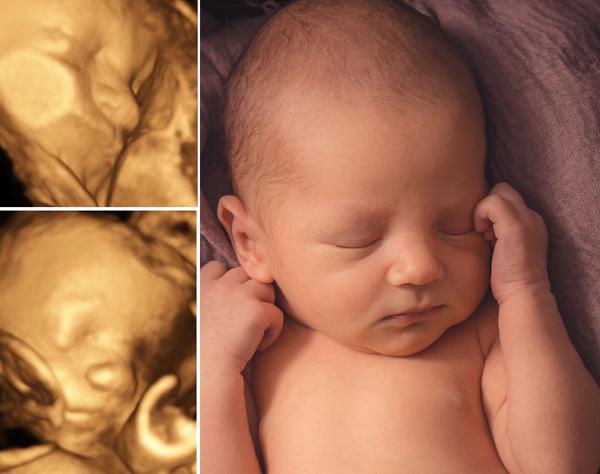

Jo dr mi dal 3D fotku malá nos hrozně velkej, sirokej, rozplaclej, ale bylo to v pohodě, měla malinký knoflík 🙂

Dcera měla na jednom utz místo nosu pěkný frňák a po narození po něm nebylo ani vidu. Má krásný nosík, tak se neboj. Utz muže zkreslovat ;)

Naše první holčička měla na ultrazvuku veliký nos a narodila se s krásným malým nosíkem.